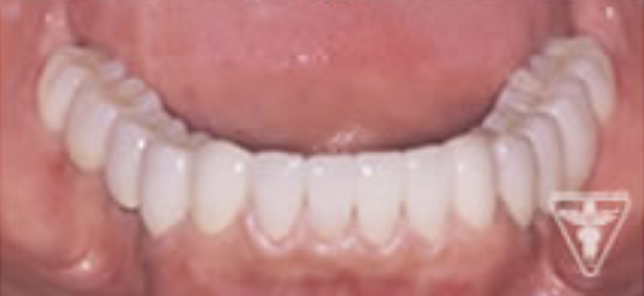

治療後

かみ合わせの深さを改善し、左下の骨を作り人工歯根で再構築しました。

前歯は、患者さんの希望でフルセラミックで対応しました。

「良く噛めて、自信をもって笑顔になれる。」と評価をいただきました。